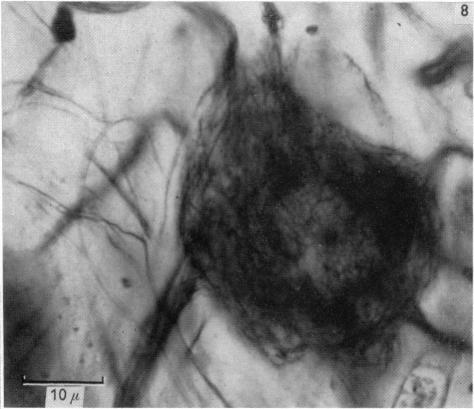

The occurrence and function of collateral sprouting in the sympathetic nervous system of the cat.

J Physiol. 1957 Jan 23;135(1):133-62. doi: 10.1113/jphysiol.1957.sp005700.